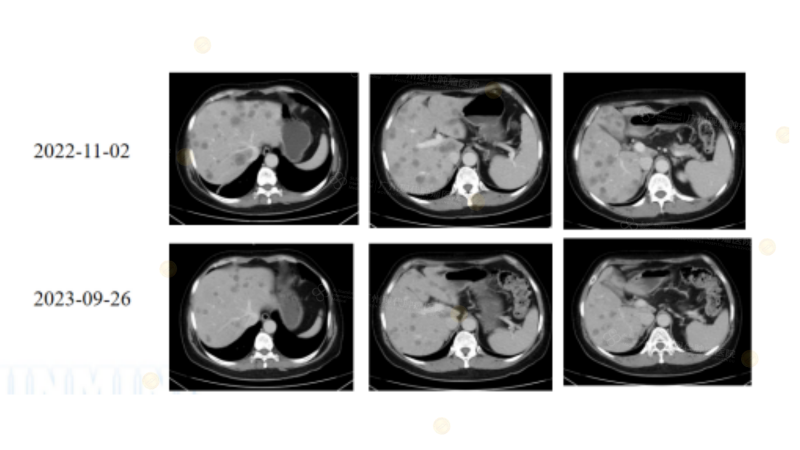

3.3. MSS CRLM患者的突破性疗效

尽管传统上MSS被认为“难获益”,但本院病例显示:

生物治疗+ 靶向 + 局部治疗在部分患者中实现显著缩瘤,甚至接近完全缓解,为MSS研究提供了重要临床证据。

(注:30岁男性直肠癌术后肝多发转移(MSS/pMMR、NRAS G12D),多线生物治疗+靶向+局部治疗(Sintilimab+HAIC+Bevacizumab+MWA)后肝转移接近CR/NED,显示MSS CRLM患者可获突破性疗效。)